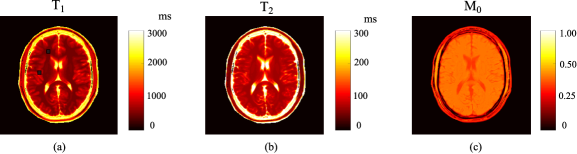

Refer to caption

Figure 5: Reconstructed parameter maps from the fully-sampled MR fingerprinting experiments (N=400𝑁400N=400 and SNR=33dBSNR33dB\mathrm{SNR}=33~{}\mathrm{dB}), using the acquisition parameters from the conventional scheme, Optimized-I, and Optimized-II. (a) Reconstructed T1subscript𝑇1T_{1} maps and associated relative error maps. (b) Reconstructed T2subscript𝑇2T_{2} maps and associated relative error maps. Note that the overall error is labeled at the lower right corner of each error map, and the regions associated with the background, skull, scalp, and CSF were set to be zero.

III-A4 Evaluation of fully-sampled experiments

We evaluated the fully-sampled MR fingerprinting experiments described in Section III.A. Note that this scenario exactly corresponds to the data model in (8), with which we calculated the CRB and performed experiment design. Specifically, we simulated the experiments at N=400𝑁400N=400 and SNR=33SNR33\mathrm{SNR}=33 dB, using the conventional scheme, Optimized-I, and Optimized-II. Fig. 5 shows the reconstructed T1subscript𝑇1T_{1} and T2subscript𝑇2T_{2} maps. As can be seen, the two optimized schemes improve the accuracy of both T1subscript𝑇1T_{1} and T2subscript𝑇2T_{2}, although the improvement is more significant for T2subscript𝑇2T_{2}. Moreover, the performance of Optimized-I is slightly better than that of Optimized-II, consistent with the CRB prediction shown before.

Fig. 6 shows the normalized bias, standard deviation, and root-mean-square error maps for the reconstructed T1subscript𝑇1T_{1} and T2subscript𝑇2T_{2} maps. As can be seen, Optimized-I and Optimized-II reduce the normalized standard deviations for both T1subscript𝑇1T_{1} and T2subscript𝑇2T_{2}, compared to the conventional scheme. Consistent with the CRB prediction and the results shown in Fig. 5, the improvement for T2subscript𝑇2T_{2} is more substantial than for T1subscript𝑇1T_{1}. Moreover, for all three acquisition schemes, the normalized standard deviation is much larger than the normalized bias, and the normalized root-mean-square error is dominated by the normalized standard deviation. The above behavior can be expected, given that the ML reconstruction is asymptotically unbiased [14].